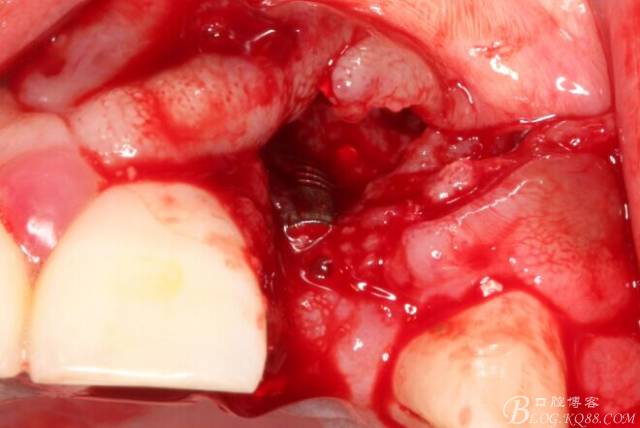

翻開后驚喜的發(fā)現(xiàn),術(shù)區(qū)成骨非常好,去除部分骨才暴露那顆長鈦釘。

取出影響種植入路的長鈦釘。

擴孔。

骨擠壓

植入植體